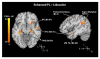

Two groups of patients with irritable bowel syndrome rated pain and underwent functional magnetic resonance imaging brain scanning during experimentally induced rectal distension (20 seconds, 7 stimuli). Group 1 was tested under baseline (natural history [NH]) and a verbally induced placebo condition, whereas Group 2 was tested under baseline and standard placebo (no verbal suggestion for pain reduction) and intrarectal lidocaine conditions. As hypothesized, intrarectal lidocaine reduced evoked pain and pain-related brain activity within Group 2. Between-group comparisons showed that adding a verbal suggestion to a placebo condition increased neural activity involved in memory and semantic processing, areas that process the placebo suggestions. These areas, in turn, are likely to influence brain areas involved in emotions and analgesia and consequently the placebo effect. These placebo suggestions also added significant decreases in activity of brain areas that process pain. The test stimulus itself seems to cue these effects and is consistent with previous explanations that somatic focus and sensory feedback reinforce expectations and other factors that mediate placebo analgesic effects.

Perspective: Expectations for pain can be verbally manipulated to produce placebo analgesia. Placebo analgesia is accompanied by decreased brain activity related to processing pain and increased brain activity that generates placebo analgesia, including semantic and memory regions. Placebo suggestions may enhance placebo analgesia by engaging a feedback mechanism triggered by the painful stimulus itself and related to brain mechanisms involved in memory and semantic processing.